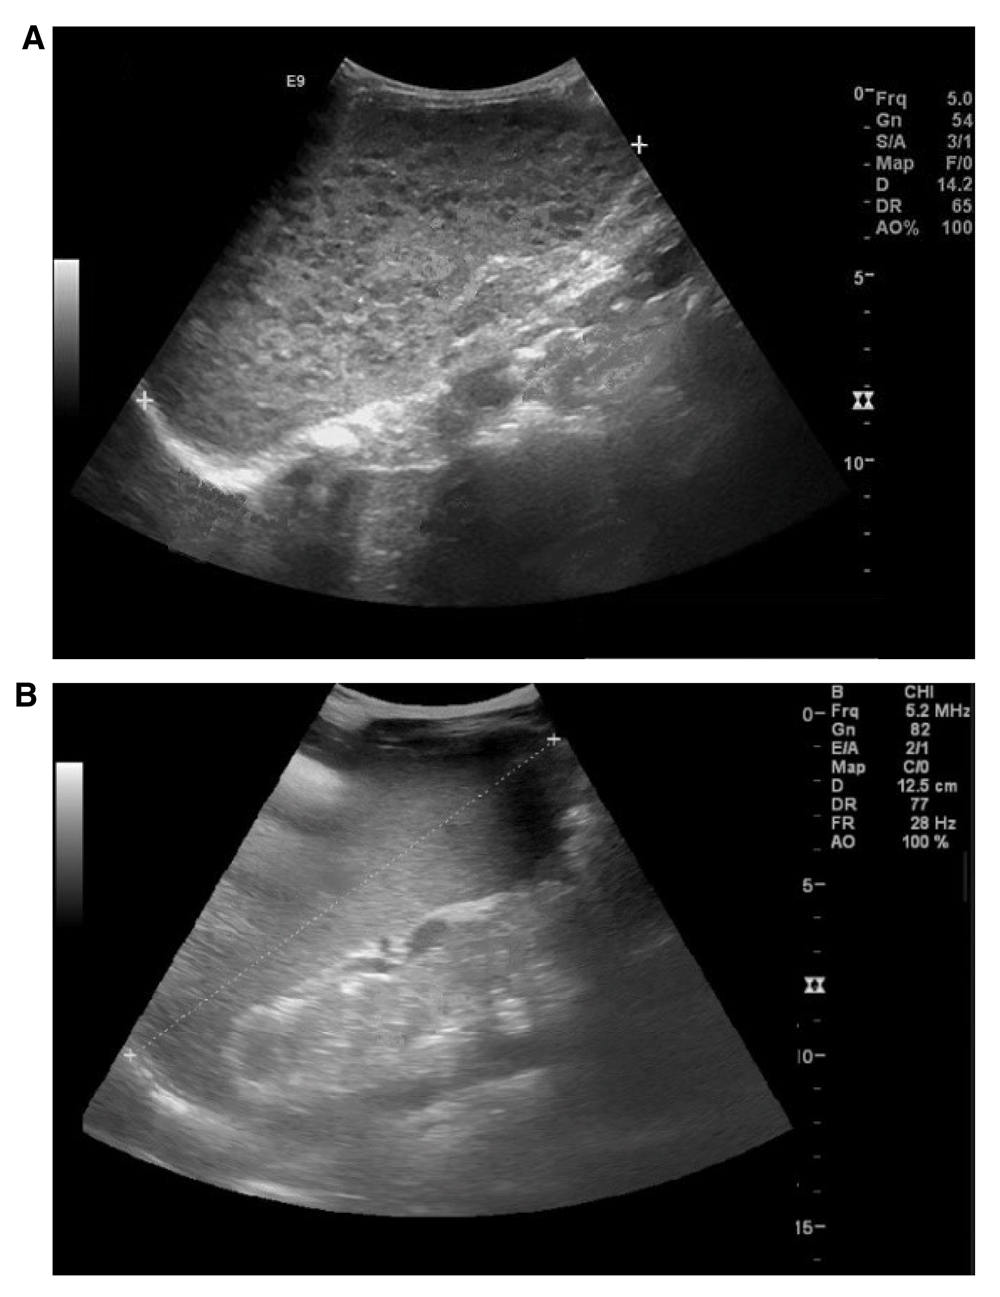

In early clinical examinations, the patient’s throat, ears, heart and lungs were functioning normally. Abdominal ultrasonography showed normal liver tissue and enlarged spleen with diffused nodules and 14.5 mm spleen span (Figure 1). Blood smear examination showed hypochromic microcytic anemia with white blood cell and platelet number reduction (Table 1).

Figure 1.

Ultrasound scan of enlarged spleen in (A) Case 1and (B) Case 2.

Ultrasonography demonstrated mild enlargement of the spleen (Figure 1). Examinations showed reduction in all blood elements (Table 1). The results of typical serological tests were negative. Bone marrow aspiration was evaluated because of pancytopenia in which no blast cell was seen. Then, due to observation of amastigotes of Leishmania parasite (Leishman-Donovan bodies) within bone marrow macrophages, and the positive DAT result (>1:3200), visceral leishmaniasis was diagnosed (Figure 2). Therefore, Amphotericin-B treatment was initiated with dose of 1 mg/kg for 21 days. After four days, the patient's fever disappeared, her general condition improved and blood cell number increased at the next month follow-up.